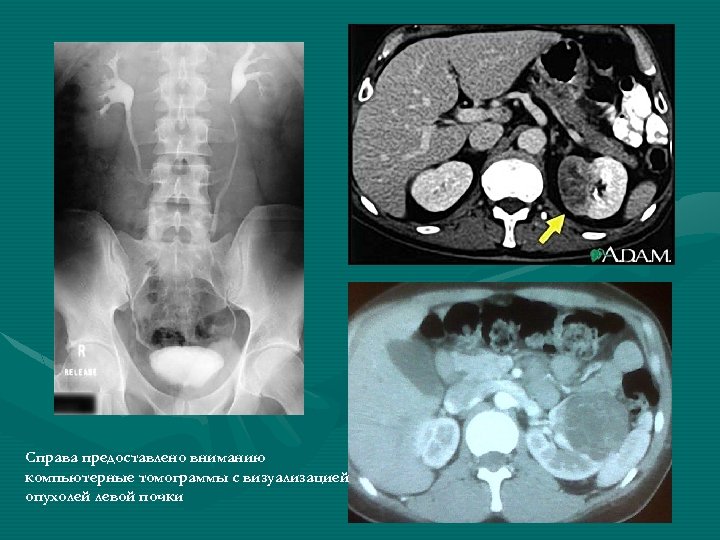

Диагностика МЕТОДЫ ДИАГНОСТИКИ РАКА ПОЧКИ ЛАБОРАТОРНЫЕ • Определение уровня гемоглобина (обычно более низкий за счет гематурии) • Определение уровня ШОЕ (обычно высокое); • Определение уровня креатинина и мочевины (функциональное состояние почек), щелочной фосфатазы (метастазы в печень, кости); • Определение показателя уровней онкомаркеров Tu M 2 - PK, SCC, CA 125 ИНСТРУМЕНТАЛЬНЫЕ • Рентгенологические исследования: - обзорная рентгенография - екскреторная урография - ретроградная пиелография - КТ ОБП (с контрастированием) - ренография. • УЗИ почек; • Тонкоигловая пункционная биопсия под контролем УЗИ; • Сцинтиграфия почек из 99 m. Тс-ДМСА; • Вазография НПВ и аорты (исключение тромба).

Справа предоставлено вниманию компьютерные томограммы с визуализацией опухолей левой почки